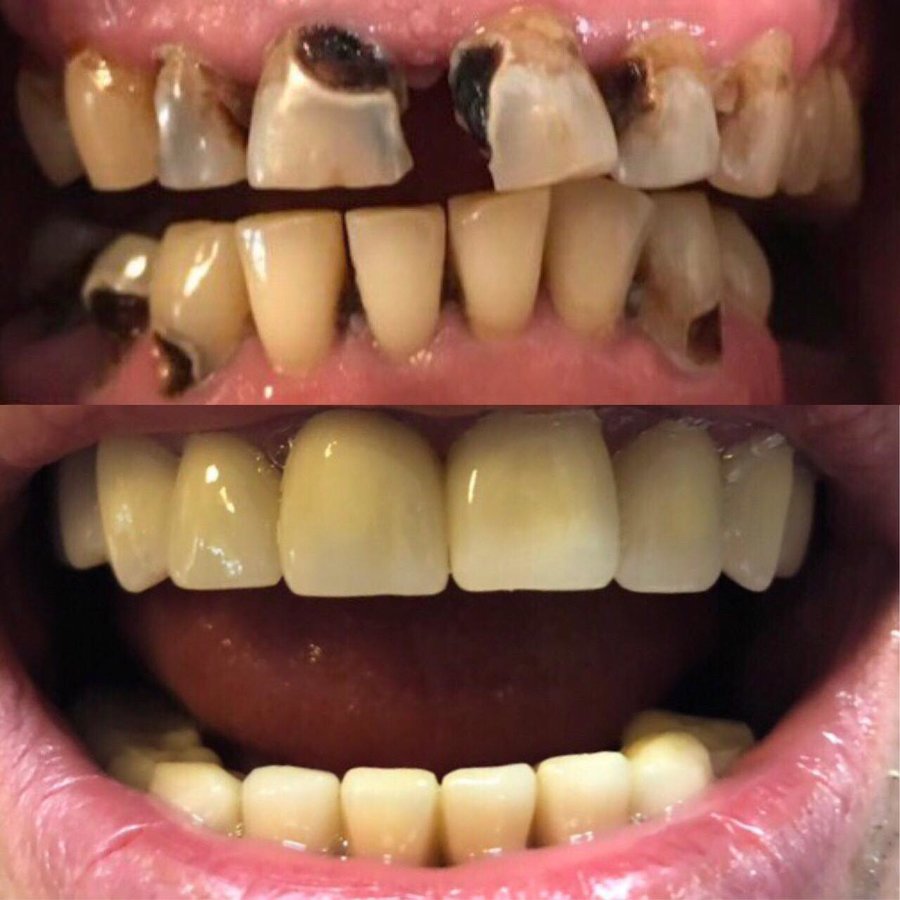

Fillings $45

Dental Bridges $33

Dental Crowns $139